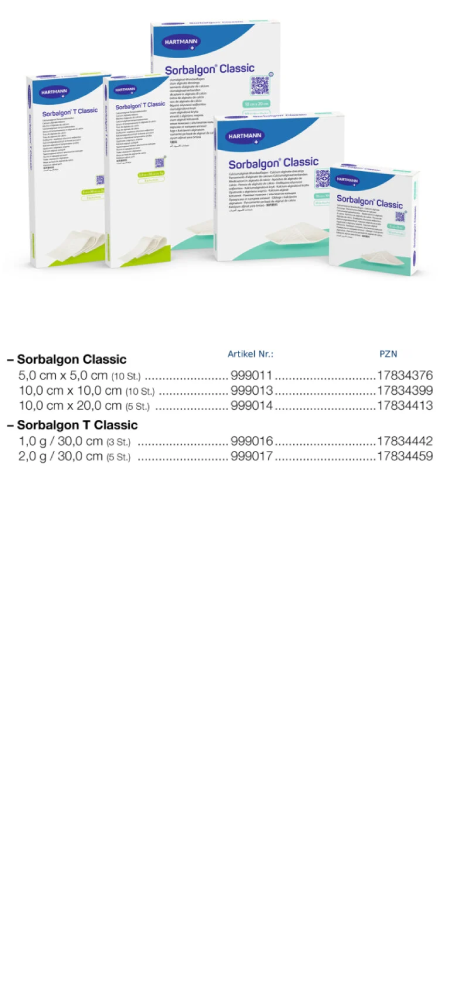

Sorbalgon Classic ![]() P und Sorbalgon T Classic sind tamponierbare, wirkstofffreie Kompressen und Tamponadestreifen aus Calciumalginat-Fasern. Keime werden während der Umwandlung in der Gelstruktur eingeschlossen.

P und Sorbalgon T Classic sind tamponierbare, wirkstofffreie Kompressen und Tamponadestreifen aus Calciumalginat-Fasern. Keime werden während der Umwandlung in der Gelstruktur eingeschlossen.

Sorbalgon Classic (PAUL HARTMANN)

Sorbalgon T Classic (PAUL HARTMANN)